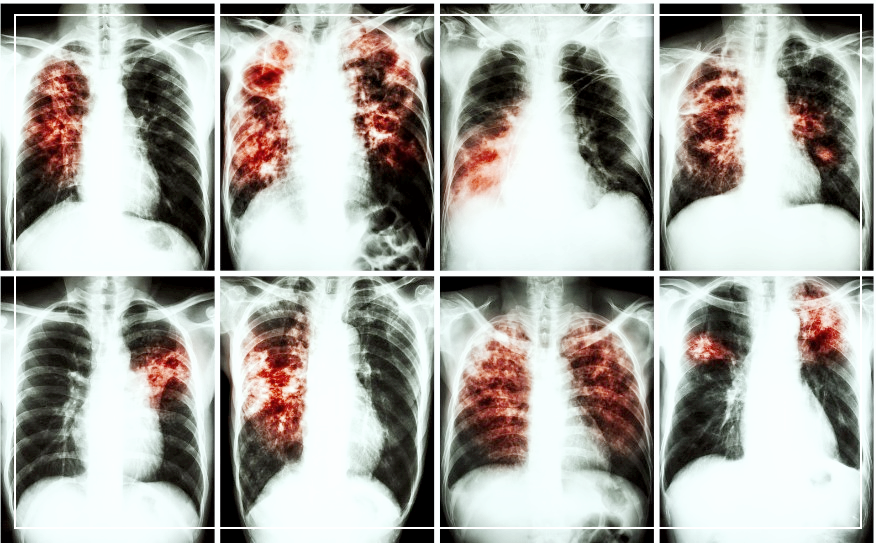

폐섬유화증은 폐조직이 점차적으로 섬유화되어 굳어지는 질병을 의미합니다. 이 상태에서 섬유화 된 조직은 정상적인 폐조직보다 훨씬 더 단단하며 탄력이 없습니다. 이로 인해 폐의 기능이 저하되며, 특히 호흡에 필요한 산소를 효과적으로 체내로 전달하는 능력이 감소합니다.

폐섬유화증 진단은 이러한 증상들을 바탕으로 의사와 상담한 후, X-선, CT, 폐기능 검사, 혈액 검사 등을 통해 확진됩니다. 초기에 증상이 뚜렷하지 않을 수 있으므로, 위 증상들 중 일부가 의심되면 전문가와 상의하는 것이 좋습니다.